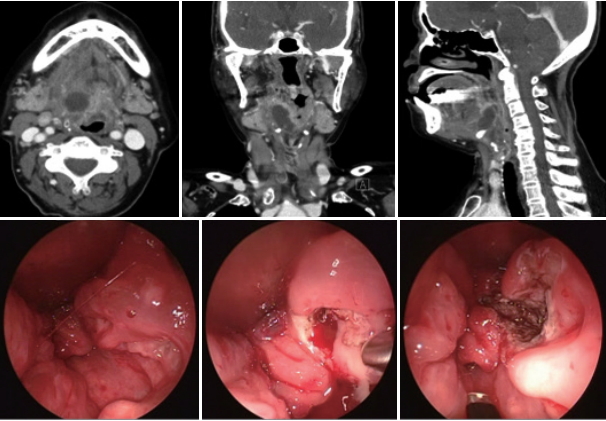

내시경 사용 여부에 따른 수술 방식고식적인 부인두 농양의 구강을 통한 절개배농은, 구강을 견인기로 벌려 측인두를 노출시키고, 진단 시 시행한 경부 CT를 보고 파악한 농양을 덮고 있다고 의심되는 측인두 점막을 통해 18게이지 바늘을 흡인하여 고름의 존재를 확인한 후, 수직으로 절개하여 배농한다. 내시경을 이용한 경우에도, 동일하게 구강을 견인기로 벌려 측인두를 노출시키고, 농양을 덮고 있다고 의심되는 부위를 내시경을 보면서 바늘흡인을 시행한다. 바늘흡인상 고름을 확인하면 동일하게 수직으로 절개하여 배농한다. 바늘흡인상 고름을 확인하지 못하였지만, CT상 농양이 명확하며, 측인두나 후두 인접 점막하에 농양이 위치한 경우는 고주파수 기구인 Coblator Evac(Arthrocare ENT, Sunnyvale, CA, USA)을 이용하여 주변 인두 점막과 점막하 조직을 넓게 절제하여, 농양을 덮고 있는 조직을 얇게 하면서 농양을 찾아나갔다(Fig. 1). 출혈이 있는 경우는 Coblator를 이용하여 지혈시켰으며, 가능하면 배액관을 삽입하였고, 배액관을 삽입하기 어려운 부위는 절개 부위 점막을 넓게 제거하여 넓혔다(Fig. 1).

본 연구에서 내시경을 이용하였을 경우에는 이용하지 않았을 때보다 더 깊은 곳에 위치한 농양까지도 배농시킬 수 있었다. 다만 본 연구가 후향적 연구로서, 저자들이 농양의 깊이가 깊을 경우, 시야 확보를 위해 나안보다는 내시경을 선호하여 위와 같은 결과가 나올 수 있다. 부인두의 해부학적 하연인 설골 부위쪽 후두와 측인두 부위에도 내시경은 좋은 시야를 제공해 줄 수 있다. 측인두 점막 부종으로 해부학적 지표가 변형되고 수술 공간이 좁아진 경우에도, 내시경은 병변 부위 확대가 가능하여 공간과 깊이의 제한을 극복할 수 있다. 경구강 절개배농은 측인두의 돌출(bulging)이나, 함입(indentation)과 같은 해부학적 기준점(landmark)이 중요한 지표가 된다. CT에서 확인한 농양 부위를 덮고 있는 측인두의 이러한 해부학적 기준점들은 내시경으로 확인할 때 더 정확하게 구별할 수 있어 바늘흡인의 정확도를 높일 수 있다. 내시경과 더불어 고주파수 기구인 Coblator를 이용하면, 점막 절제와 지혈이 가능하여, 시야 확보에 더욱 유리하다. 바늘흡인에만 의존하지 않고, 농양 부위를 덮고 있는 점막이나 점막하 조직을 Coblator로 절제할 수 있어, 농양을 덮고 있는 부위를 얇게 하거나 절제하여, 농양 노출이 용이하다(Fig. 1). Coblator 기구는 점막이나 점막하 조직은 비교적 용이하게 절제가 가능하나, 근육은 쉽게 절제하지 않아, 근육 외측에 위치한 주요 혈관의 손상을 피할 수 있는 장점이 있다. 내시경을 이용하여 설근부와 설편도 절제 방식은 이미 수면 수술 분야에서 활발히 이루어지고 있다[20]. 우리 연구에서도 위의 방식을 채용하여 설골 주변까지도 접근이 가능하였다.

NotesAuthor Contribution Conceptualization: Myoung Su Choi. Data curation: Myoung Su Choi. Formal analysis: Dong Sik Chang. Investigation: Jun Lee, So Young Choi. Methodology: Myoung Su Choi. Project administration: Dong Sik Chang. Resources: Dong Sik Chang. Software: Myoung Su Choi. Supervision: Dong Sik Chang. Validation: Myoung Su Choi. Visualization: Myoung Su Choi. Writing—original draft: Myoung Su Choi. Writing—review & editing: Myoung Su Choi. Fig. 1.Enhanced CT scan revealed an ovoid abscess pocket involving the right parapharyngeal and paralaryngeal space, causing significant airway narrowing (upper). Incision and drainage of the abscess was performed with Evac Coblator (Arthrocare ENT) and endoscope via transoral approach (lower). Fig. 2.Measuring depth of the abscess at which the horizontal line of the lower margin of it meets the cervical vertebrae in CT. Table 1.Clinical characteristics of patients